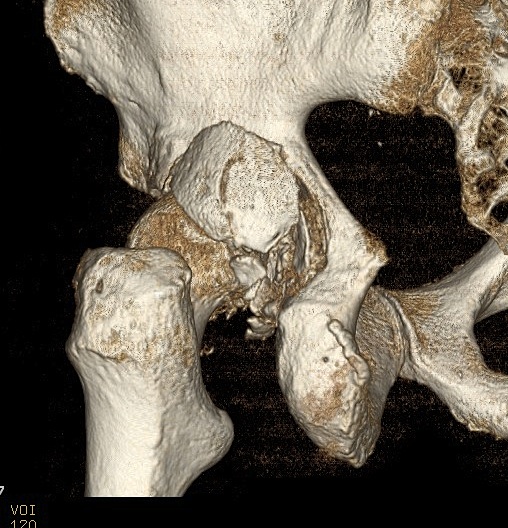

Classification

Direction

1. Medial / Central

- really medial displacement with acetabular fracture

2. Anterior

- pubic / obturator / perineal

3. Posterior

Pathoanatomy

Capsule & Ligamentum teres torn

Labral tears & muscular injuries also occur

Y / iliofemoral ligament often intact with posterior dislocation

- blocks reduction

- bony fragments also block reduction

Clinical Features / Xray

Posterior dislocation

- leg shortened, flexed, adducted & internally rotated

- head small on xray

Anterior dislocation

- leg short and externally rotated

- head larger on xray

Check NV status / sciatic nerve

3. Screen for retained fragments

Compulsory CT

- xray will not detect fragments < 2mm

Non-concentric Reduction

Esssential to obtain X-ray and CT after reduction

X-ray

- head - teardrop distance must equal contralateral side

CT

- only with CT can < 2mm fragments be seen